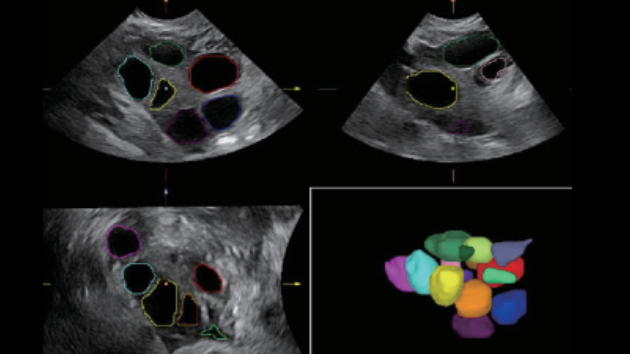

The Nuewa I9 Elite Edition, dedicatedly designed for women and neonatal healthcare, providing an innovative experience from inside out. These innovations are developed based on in-depth insights into complex clinical scenarios, providing accurate and timely answers as well as outstanding efficiency and remarkable user experience